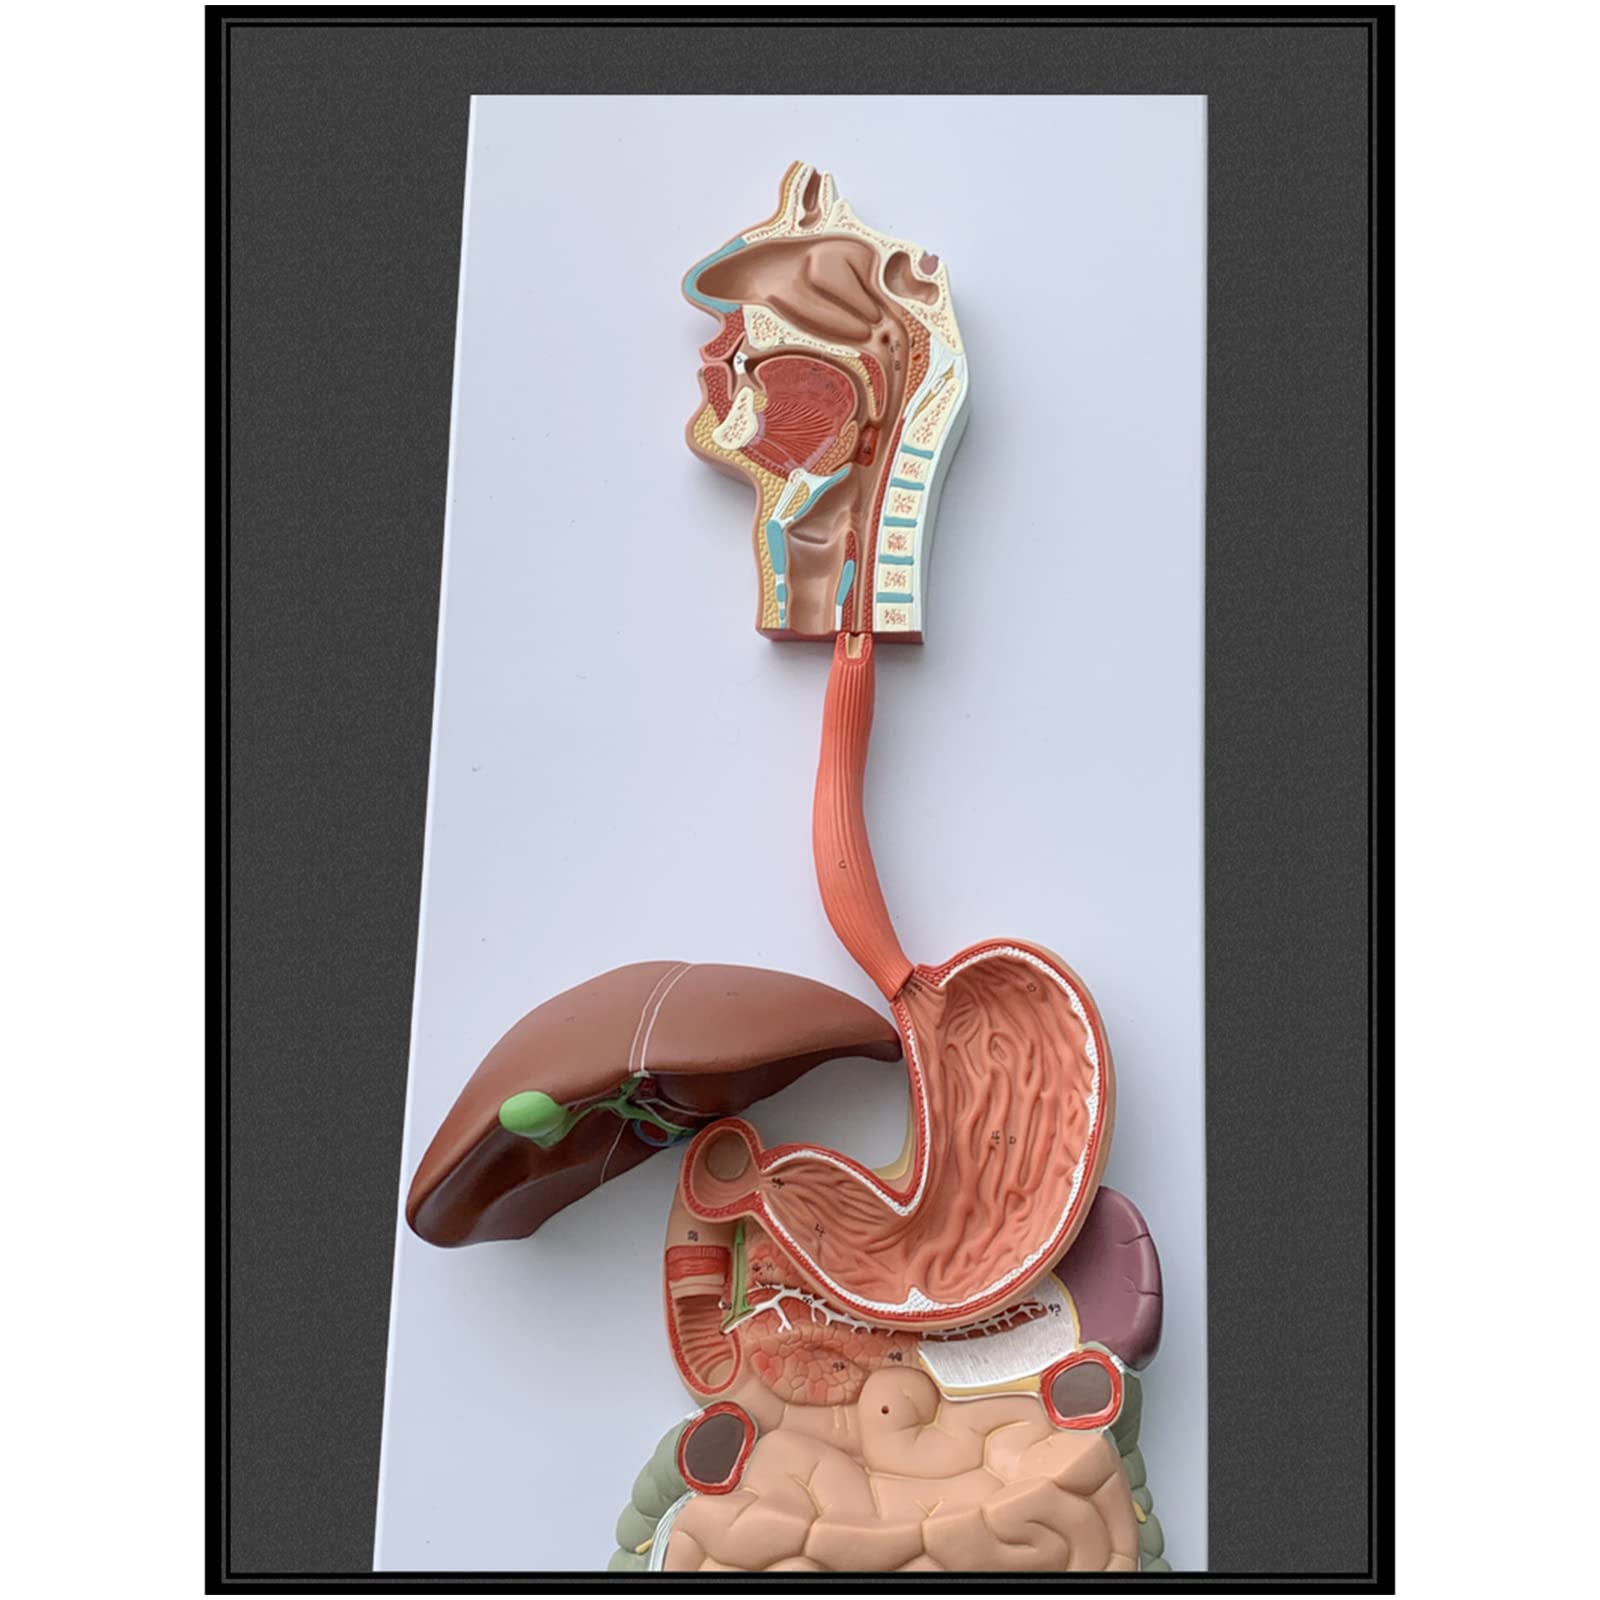

- ENHANCE PATIENT EDUCATION - Empower your clients with clear visual aids for better understanding!

- INTERACTIVE LEARNING EXPERIENCE - Disassemble and explore the digestive system like never before!

The Human Digestive System Model is a life-size, three-dimensional representation of the human digestive tract, designed for educational purposes. It features disassemblable parts for interactive learning and is made from durable, anti-corrosive PVC material, making it an essential tool for anatomy students, educators, and healthcare professionals.